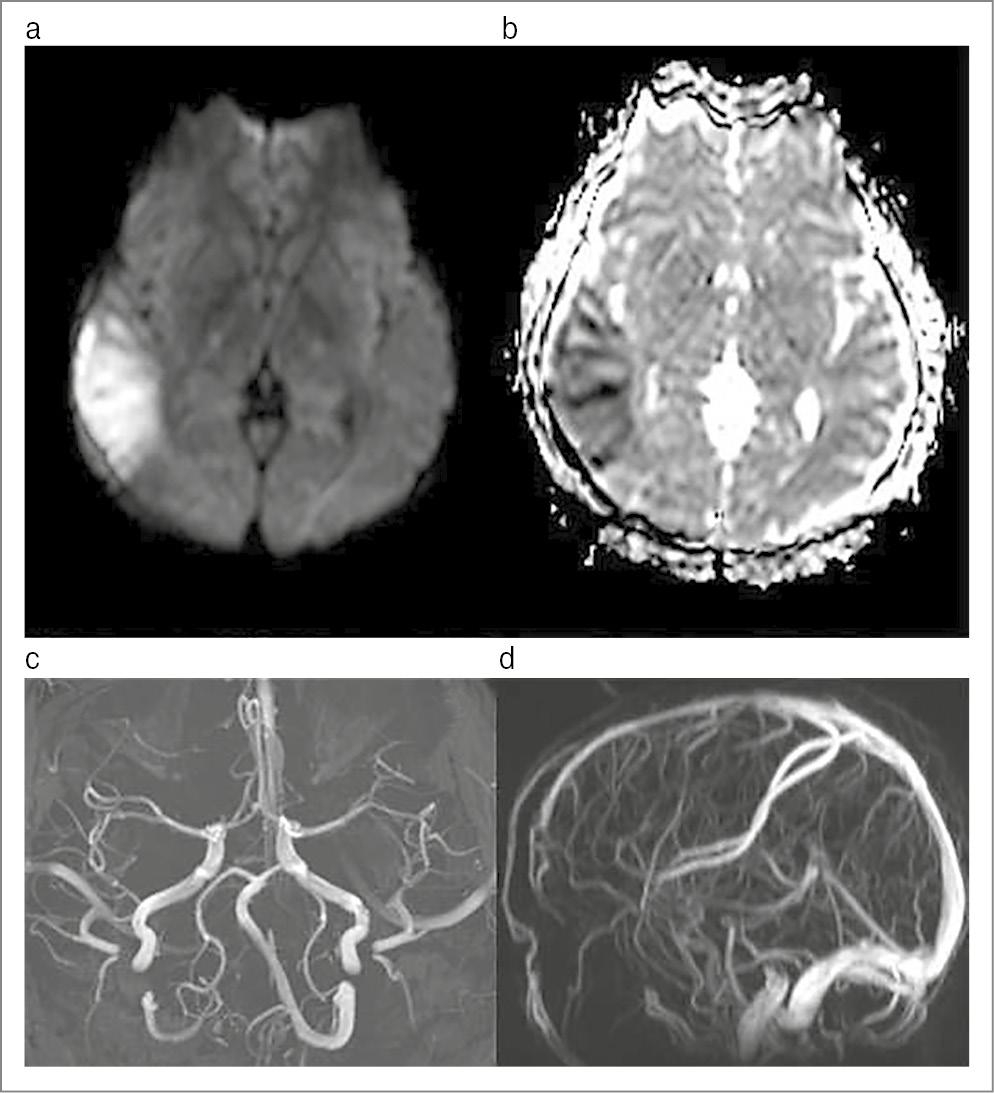

Пациентка Х., 27 лет. В анамнезе с подросткового возраста МБА, редкие приступы. Получает комбинированное контрацептивное средство (препарат, содержащий эстроген+гестаген) по назначению гинеколога. 10 января 2022 г. остро развилась интенсивная ГБ в правой половине головы (по Визуальной аналоговой шкале 8 баллов) без тошноты и рвоты, перед приступом ГБ появлялись «белое пятно» перед правым глазом с нечеткостью зрения и легкое онемение левой руки. Зрительные нарушения регрессировали в течение суток, сенсорные – в течение 3 дней. Интенсивная ГБ сохранялась около 10 дней, пациентка не обращалась за экстренной помощью, принимала нестероидные противовоспалительные препараты с временным уменьшением интенсивности цефалгии (ГБ не купирована). После амбулаторного обращения к неврологу направлена на МРТ ГМ, которое выявило признаки ишемического инсульта в правой теменно-височной области – гиперинтенсивность на диффузно-взвешенной МРТ тела (ДВИ) и гипоинтенсивность на ADC-картах (рис. 4, a, b). По результатам МР-ангиографии патологии артерий и венозных структур не обнаружено (рис. 4, c, d), гиперинтенсивности артерий на FLAIR не отмечено. Пациентка госпитализирована в первичное сосудистое отделение, поиск причин инсульта (КТ-ангиография, трансторакальная ЭхоКГ, холтеровский мониторинг ЭКГ, микропузырьковая проба, базовый лабораторный скрининг) патологии не выявил, анализы на основные тромбофилии (включая оценку на антифосфолипидный синдром) также отрицательные. В последующем пациентку беспокоили приступы МБА со средней частотой 1 раз в месяц, успешно купирующиеся ибупрофеном. После установления диагноза мигрень-ассоциированного инсульта пациентке рекомендовано не использовать триптаны для контроля приступов ГБ, а после совместной консультации с гинекологом отменен оральный контрацептив.

Рис. 4. Клинический случай №4: a – ДВИ; b – ИКД-карты МРТ; c – МР-ангиография (TOF); d – МР-венография (TOF).

В четвертом клиническом случае у пациентки наблюдалась типичная мигренозная ГБ с пролонгированным неврологическим дефицитом, а первичная МРТ, выполненная отсроченно, выявила типичный инфаркт в бассейне правой средней мозговой артерии. Ипсилатеральные зрительные симптомы предположительно объясняются преходящей ретинальной ишемией, однако картина глазного дна в остром периоде не исследовалась. Другим объяснением могла бы быть сочетанная эмболия в правый каротидный бассейн, однако поиск ее источников показал отрицательный результат. Этот случай поддерживает критику критериев Международной классификации головных болей 3-го пересмотра [5] по мигренозному инфаркту, так как они требуют наличия у пациентов МА, не допуская возможности инсульта при МБА. Для «обхода» данных традиционных критериев некоторые эксперты используют термин «мигрень-ассоциированный инсульт» [38]. Мигренозный инсульт наблюдается редко – на его долю приходится 0,8% всех случаев инсульта, однако у молодых пациентов каждый десятый инсульт может быть мигрень-ассоциированным [39, 40]. Возможные причины мигренозного инсульта включают вазоконстрикцию, углубленную корковую депрессию со снижением регионарного кровотока, эндотелиальную дисфункцию и протромботические состояния [41, 42]. Роль последнего фактора усилена в нашем случае использованием гормонального контрацептива, а сочетание симптомов ишемии со стороны ГМ и сетчатки (ипсилатерально) свидетельствует о распространенной корковой депрессии/вазоконстрикции [43].